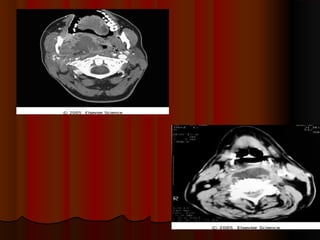

INFECTION OF INFRATEMPORALINFECTION OF INFRATEMPORAL

SPACESPACE

 Infective complications can develop and presentInfective complications can develop and present

following the extraction of clinically non-infected teethfollowing the extraction of clinically non-infected teeth

 Infratemporal space infection is a rare complication ofInfratemporal space infection is a rare complication of

dental extractiondental extraction

 The cardinal clinical signs of maxillary andThe cardinal clinical signs of maxillary and

mandibular neurosensory deficit may not bemandibular neurosensory deficit may not be

immediately apparentimmediately apparent

 The diagnosis, as in this case, can only be confirmedThe diagnosis, as in this case, can only be confirmed

using scanning imaging modalities (CT or MRI)using scanning imaging modalities (CT or MRI)

Clinical features :-Clinical features :-

Severe trismusSevere trismus

Buldging of temporalis muscleBuldging of temporalis muscle

Swelling extraorally over the region of sigmoiSwelling extraorally over the region of sigmoi

notch and intraorally in tuberosity region.notch and intraorally in tuberosity region.